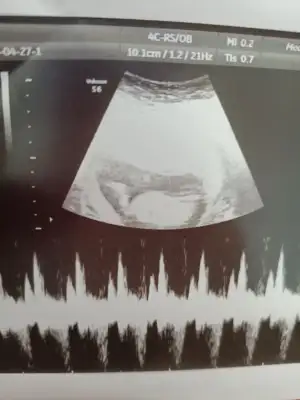

Benim bebeğime de bakar mısınız 12+4 günlük burada doktor cinsiyetini göremedii sizce nedir

Eklentiler

• 7B4DCC87-F158-4690-9BEE-AF5E7C4673AA.webp

7B4DCC87-F158-4690-9BEE-AF5E7C4673AA.webp

69,6 KB · Görüntüleme: 60